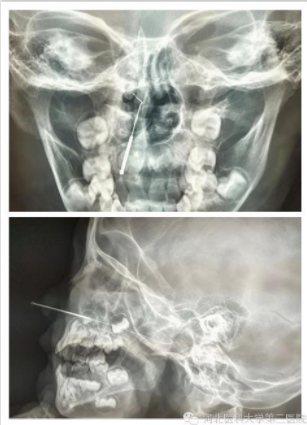

【耳鼻咽喉二科】米粒误入“歧途” “工具”秒变凶器